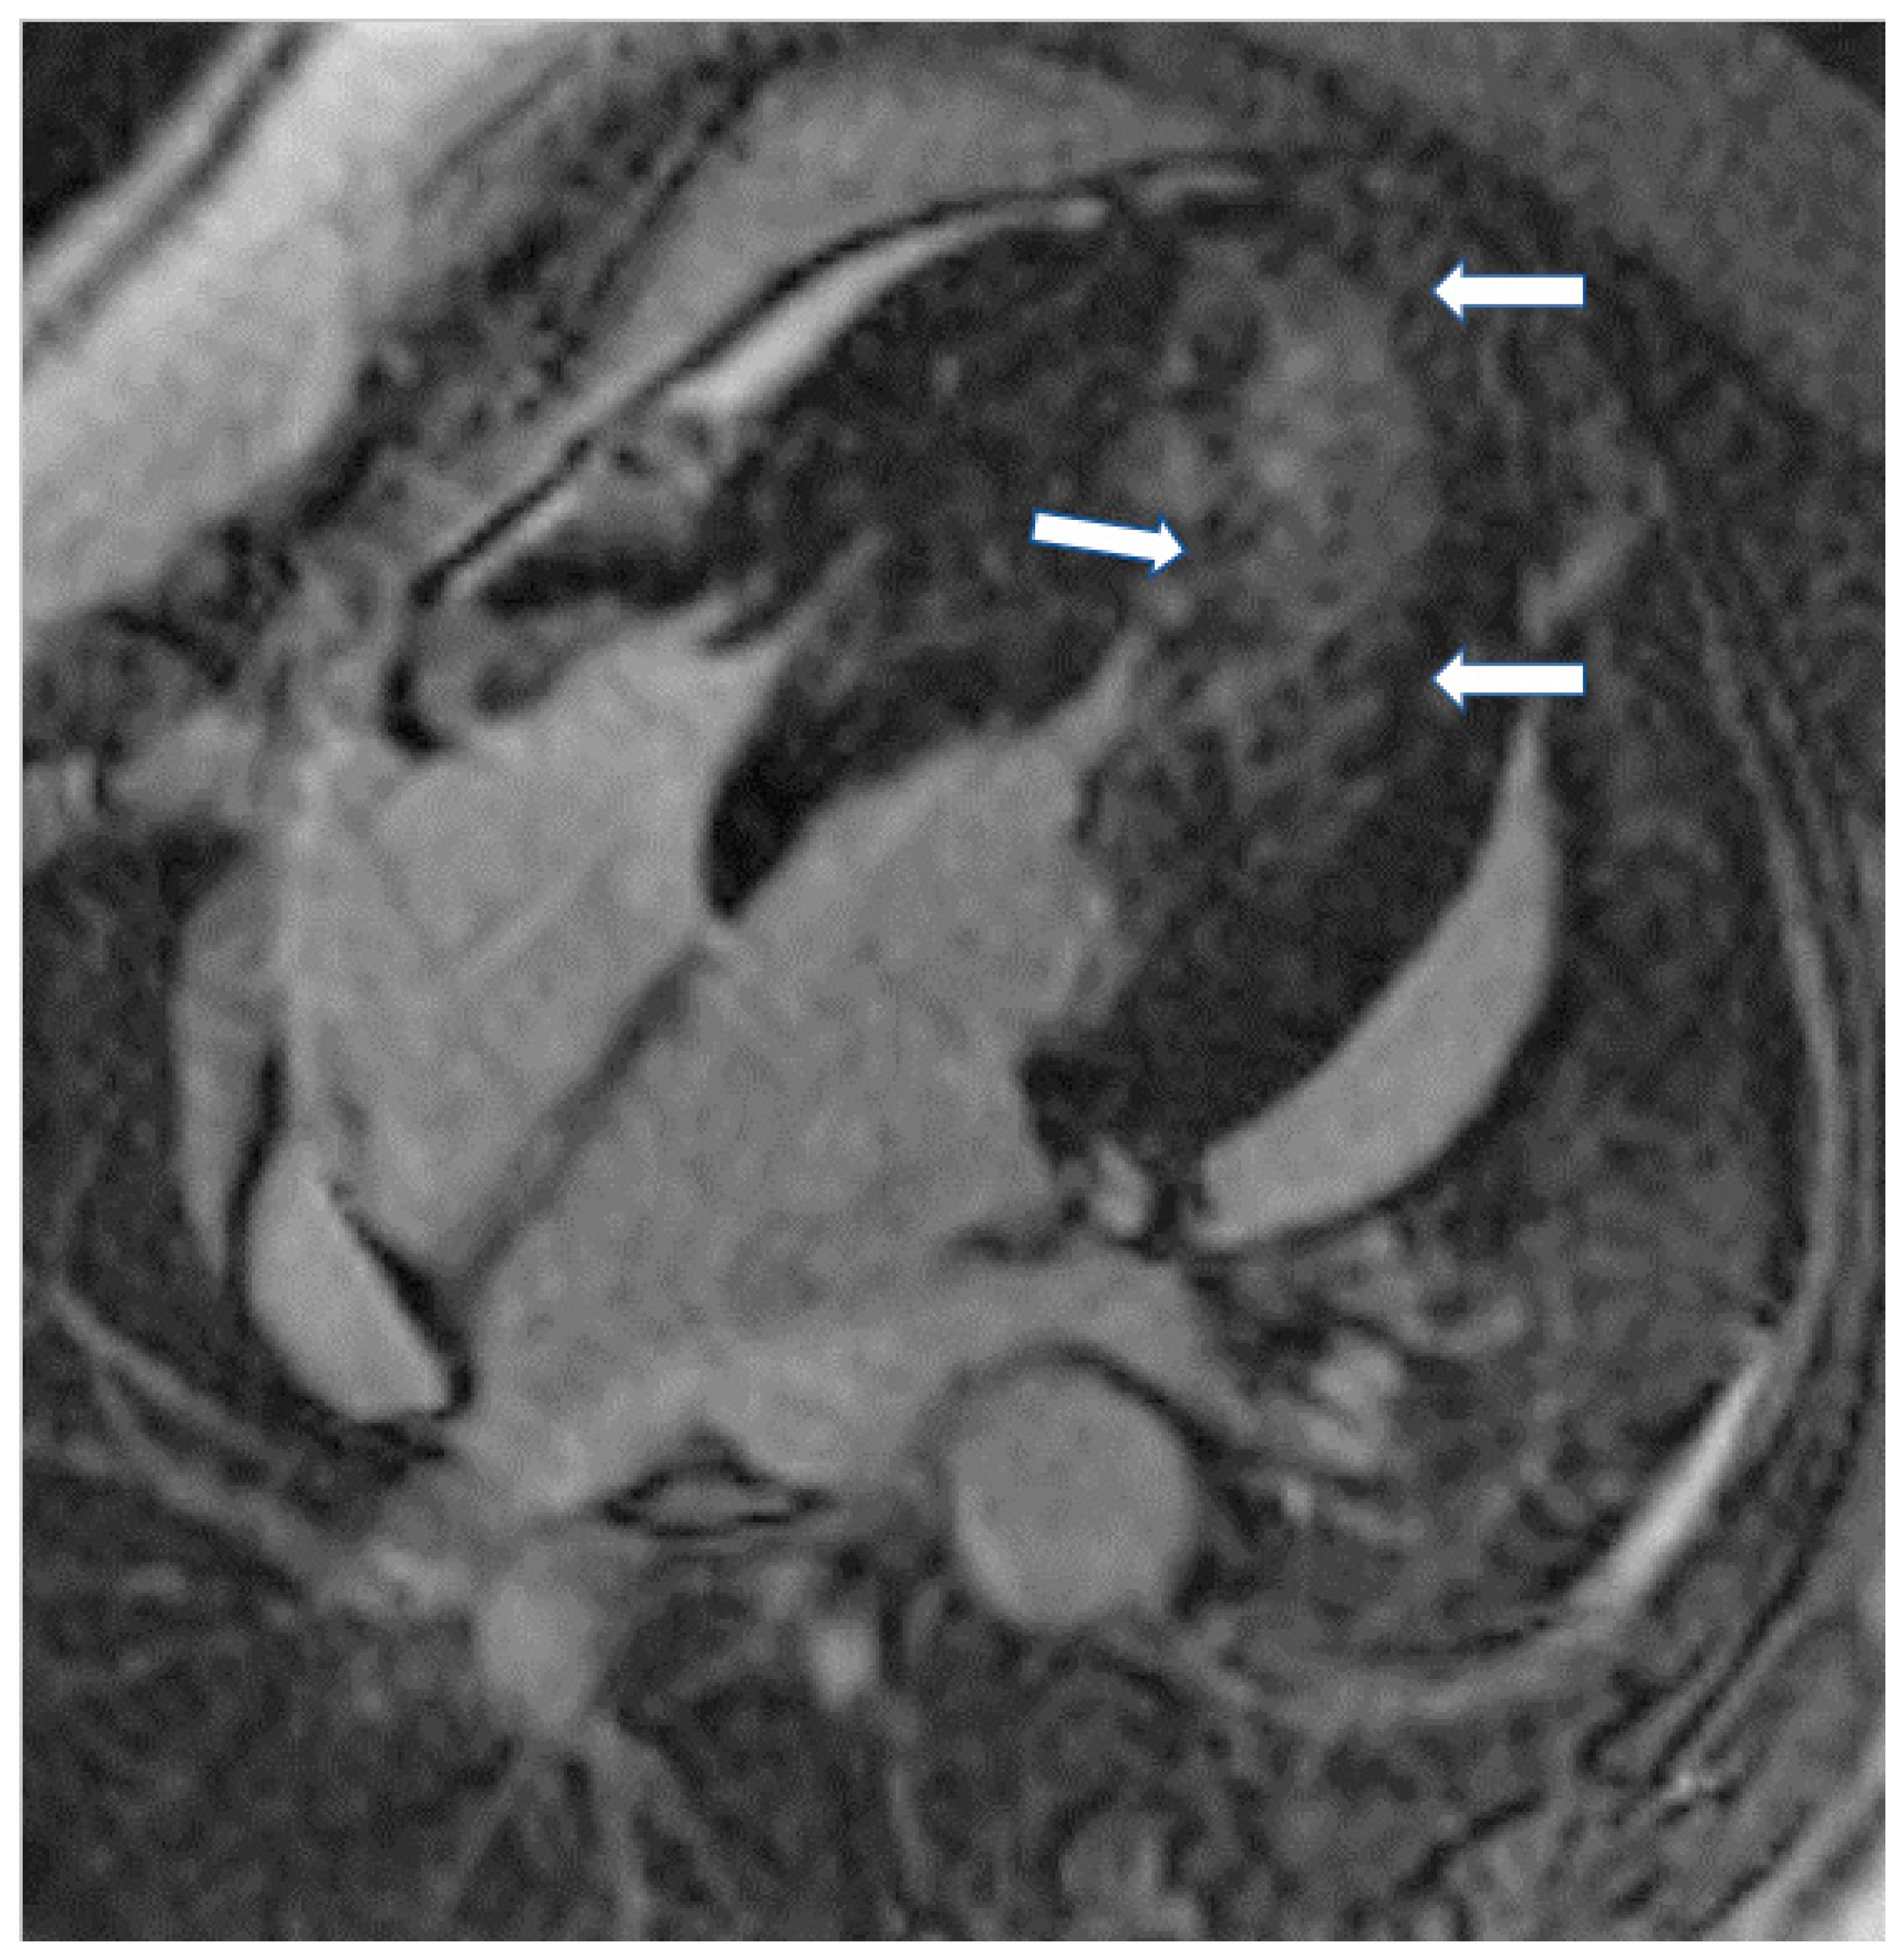

- T1-weighted images (T1-W) and late gadolinium enhancement (LGE): T1-W imaging provides information for a morphological assessment of the heart. Late gadolinium-enhanced T1-W images (LGE), taken 10–15 min after gadolinium-based contrast administrations using inversion recovery pulse sequences, allows for the detection of myocardial replacement fibrosis (scar) (Figure 1) [13]. LGE may also detect marked extracellular interstitial expansion in association with amyloidosis (amyloid deposition and fibrosis) and in pulmonary hypertension (myocardial disarray with increased collagen content without focal replacement fibrosis). In myocarditis, LGE mainly reflects inflammation, combined with or without fibrosis [13]. In the acute phase of myocarditis, LGE correlates with necrosis (associated with edema as assessed by T2 mapping), while in the chronic phase, it corresponds to fibrosis (with less or no edema) [13]. Thrombi (if not organized) do not accumulate contrast agents, making LGE ideal in excluding recent thrombi [14].

Figure 1. (A) Short-axis LGE image showing myocardial infarction (arrows) in the inferolateral wall of LV. (B) Matching native T1 mapping of the same patient.Myocardial infarction is characterized by subendocardial or transmural LGE in the distribution of epicardial coronary arteries. Subepicardial or patchy LGE usually in the inferolateral wall is characteristic of myocarditis. Finally, diffuse subendocardial LGE that does not follow the typical distribution of epicardial coronary arteries is often associated with microvascular coronary artery disease, vasculitis, antiphospholipid syndrome, and endocrine disorders, such as Cushing syndrome and autoimmune thyroid disease [13]. - (b)